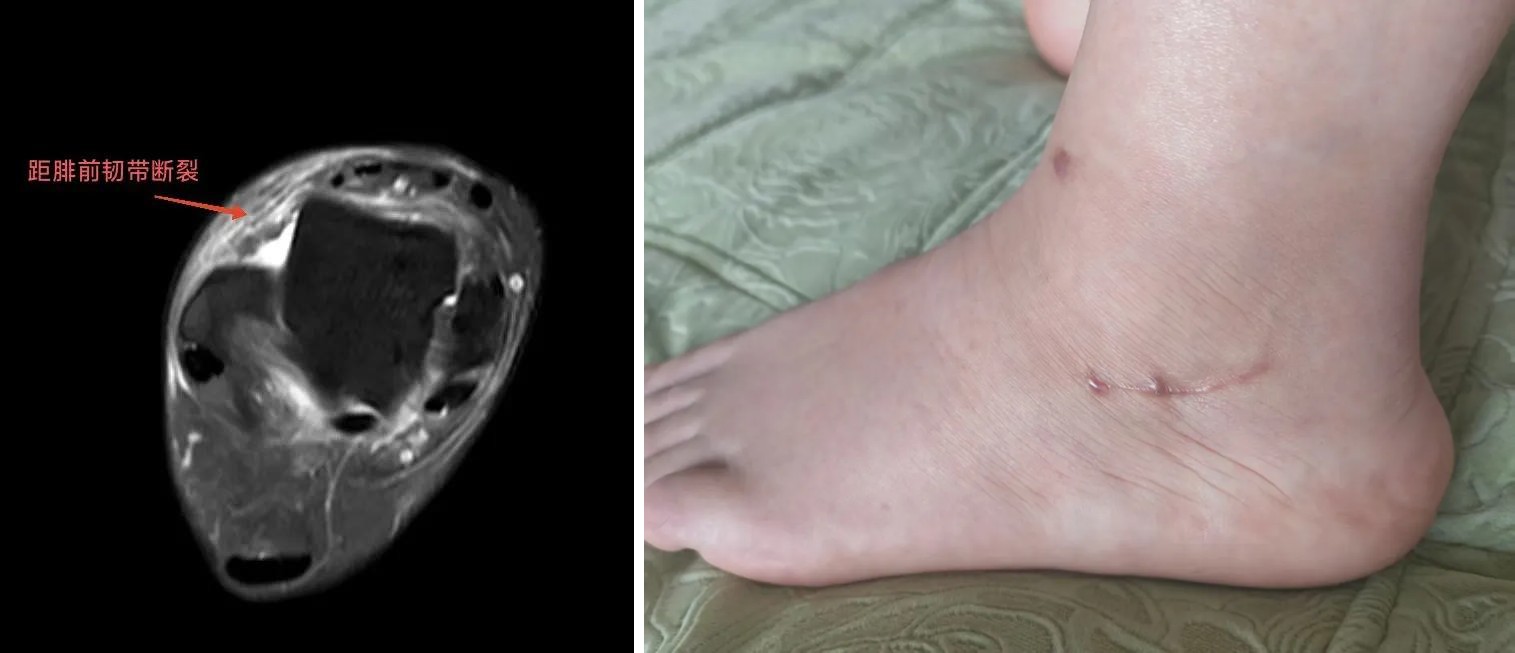

患者邓女士,因车祸导致脑外伤住院,长期卧床治疗。2个月后下地行走,发现踝关节疼痛伴不稳。临汾市人民医院足踝外科专科门诊通过核磁检查,发现患者距腓前韧带断裂。

手术采用一个小切口(3cm),完成腓骨短肌腱取腱和距腓前韧带重建两个手术,并且只取了腓骨短肌的三分之一肌腱,即完成了重建韧带任务,还保留了三分之二原肌腱,可谓一举两得。

术后两个月,患者门诊复查,恢复良好,踝关节稳定性良好,疼痛消失。